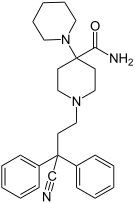

Pirinitramides

Structures

| Pirinitramides | ||||

|---|---|---|---|---|

|

| |||